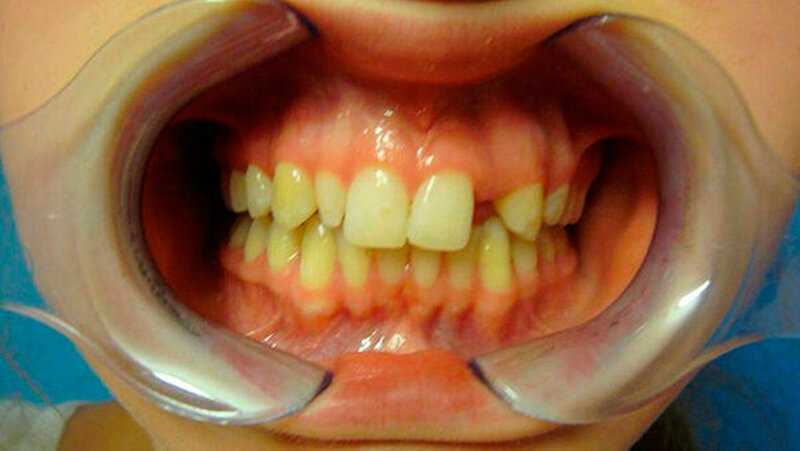

Eine 20-jährige Patientin stellte sich erstmalig zur Implantat- und Distraktionsberatung in unserer Abteilung für Mund-, Kiefer- und Gesichtschirurgie vor. Diagnostisch lagen eine mandibuläre Retrognathie, retinierte und verlagerte Zähne 18, 28, 38 und 48, ein Zapfenzahn 12, ein fehlender Zahn in regio 022, eine Mittellinienverschiebung und ein Engstand der Oberkieferfront vor (Abbildungen 1a bis d). Im Rahmen der klinischen Untersuchung und basierend auf dem Auswertungsergebnis der Digitalen Volumentomografie (DVT) führten wir bei der Patientin im Hinblick möglicher therapeutischer Maßnahmen eine differenzial-therapeutische Beratung durch.

Klinisch als auch radiologisch lag eine konvergierende Wurzelstellung der Zähne 21 und 23 vor. Eine unkomplizierte implantatprothetische Versorgung der Lücke 022, das heißt ohne Verletzung der benachbarten angulierten Zähne, erschien nicht möglich. Die Schwierigkeit bestand darin, die Lücke 022 durch körperliche Bewegung der Zähne zu öffnen, was sich bislang mittels festsitzender Apparatur als frustran erwiesen hatte. Der Patientin wurde aufgrund der vorliegenden Diagnose eine parodontal akzelerierte osteogenetische Orthodontie (PAOO) im Bereich des linken Oberkiefers empfohlen.

Darüber hinaus wünschte sich die Patientin, auch die Lücke mit dem Zapfenzahn 12 zu öffnen, damit weitere Korrekturen aus ästhetischen Gründen durchgeführt werden konnten. Auf den Zapfenzahn 12 sollte eine entsprechend größere Krone gesetzt werden oder gegebenenfalls eine Extraktion und eine Implantation erfolgen. Wir stellten der Patientin frei, auch dort das PAOO-Verfahren einzusetzen. Die Durchführung beider Korrekturen erschien in Vollnarkose und mit gleichzeitiger Entfernung der Weisheitszähne indiziert.